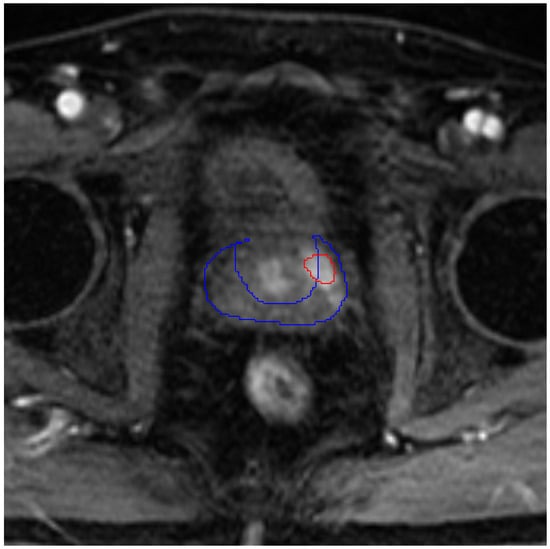

- Image analysis techniques (segmentation, classification, retrieval, and generation);

- Applications in healthcare and medical image analysis;

- image segmentation